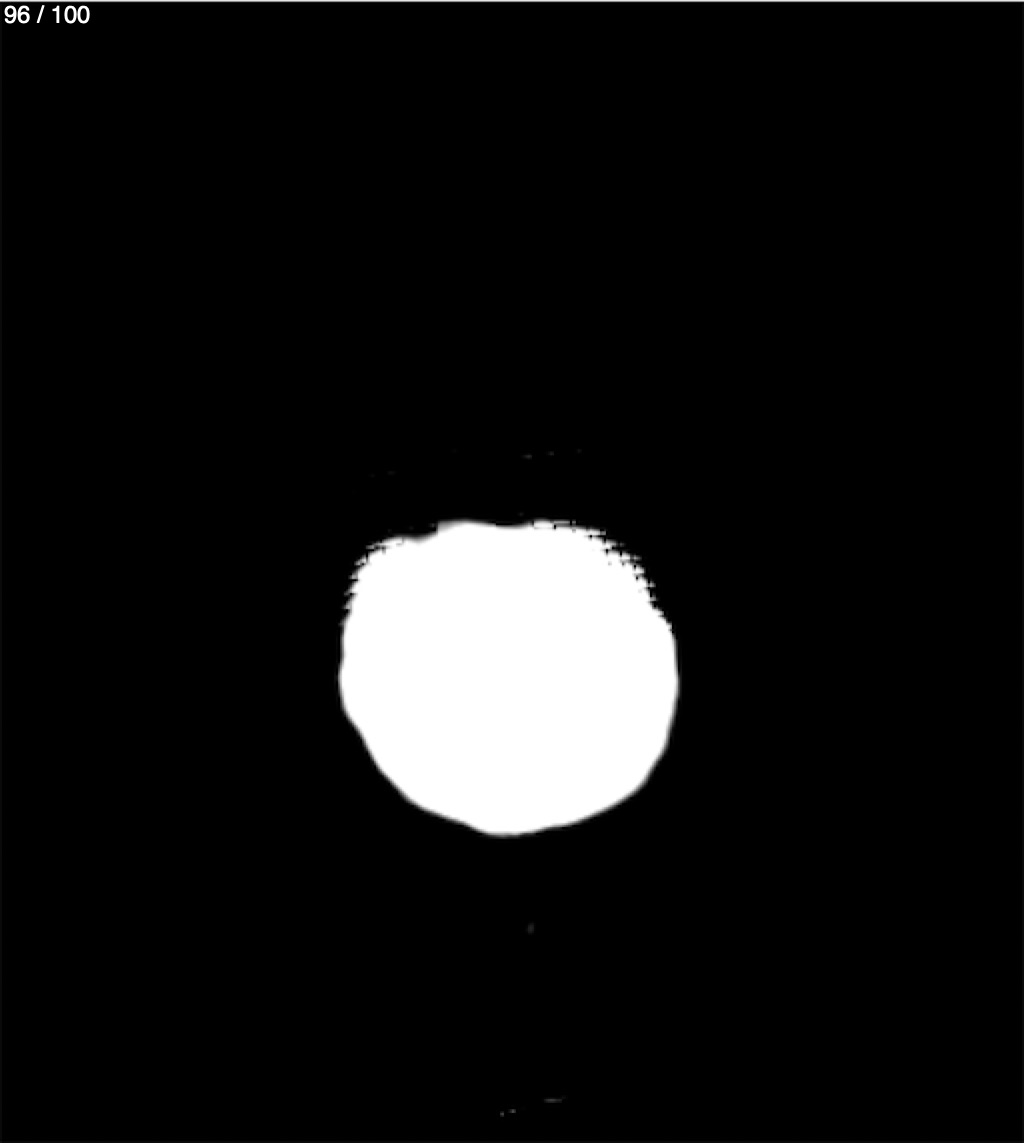

Jose Sosa Martinez 66A - Angiotac Craneo